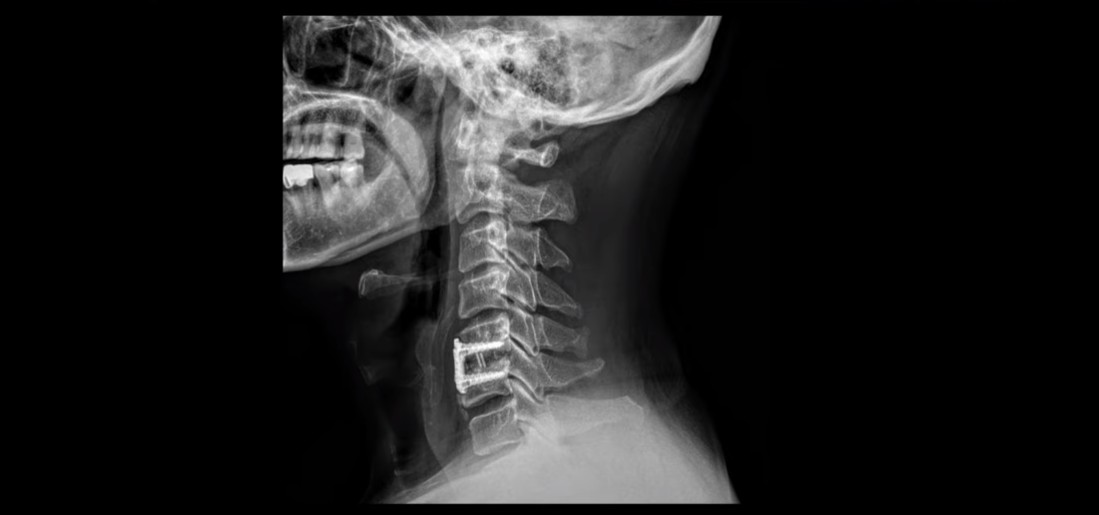

MRI를 보시면 목 5번 6번 마디에 나사가 박힌 유합술이 되어있습니다.

제자리에 나사가 잘 박혀 있고 유합술은 크게 문제가 없는 것으로 보입니다.

이분도 X-ray를 보면 완전한 일자목, 거북목 환자입니다.

이런 목의 형태를 가지고 있으면 만성적으로 목과 어깨가 아플 가능성이 높습니다. 앞으로 밀려나간 머리를 목 근육이 붙잡고 있어야 하기 때문에 목, 어깨 근육이 뭉치면서 아프기 쉽습니다. 또 목 근육과 머리 뒤쪽 근육이 연결되어 있으므로 목 근육이 뭉치면 머리 근육도 뭉치면서 두통도 생길 수 있습니다. 또한 거북목은 목 앞쪽 근육이 짧아지면서 심하게 뭉치는데, 이 목 앞쪽 근육 사이로 얼굴 쪽으로 가는 수많은 신경과 혈관이 지나갑니다. 그래서 신경과 혈관이 영향을 많이 받기 때문에 어지럼증, 눈 통증, 눈 침침함, 이명 같은 증상이 생길 수도 있습니다.